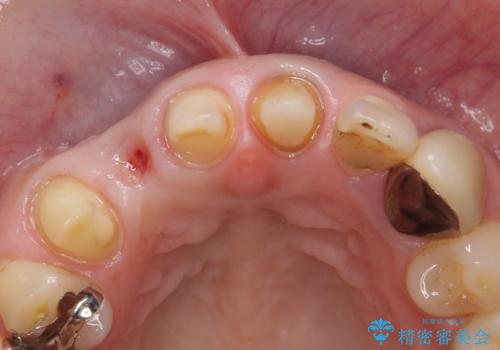

- 他院で治療したところ、右上2番目の歯の歯茎が下がってしまったので診て欲しいといらっしゃった方の症例です。

診査の結果右上2は歯根が破折しており、それが原因で骨及び歯肉の吸収が起きていました。

このまま右上2の抜歯を行うとさらに歯茎が下がる恐れがあったため、歯の挺出によって骨レベルを回復した上で抜歯し、歯槽堤保存術(抜歯窩に人工骨を填入する手術)を行いました。